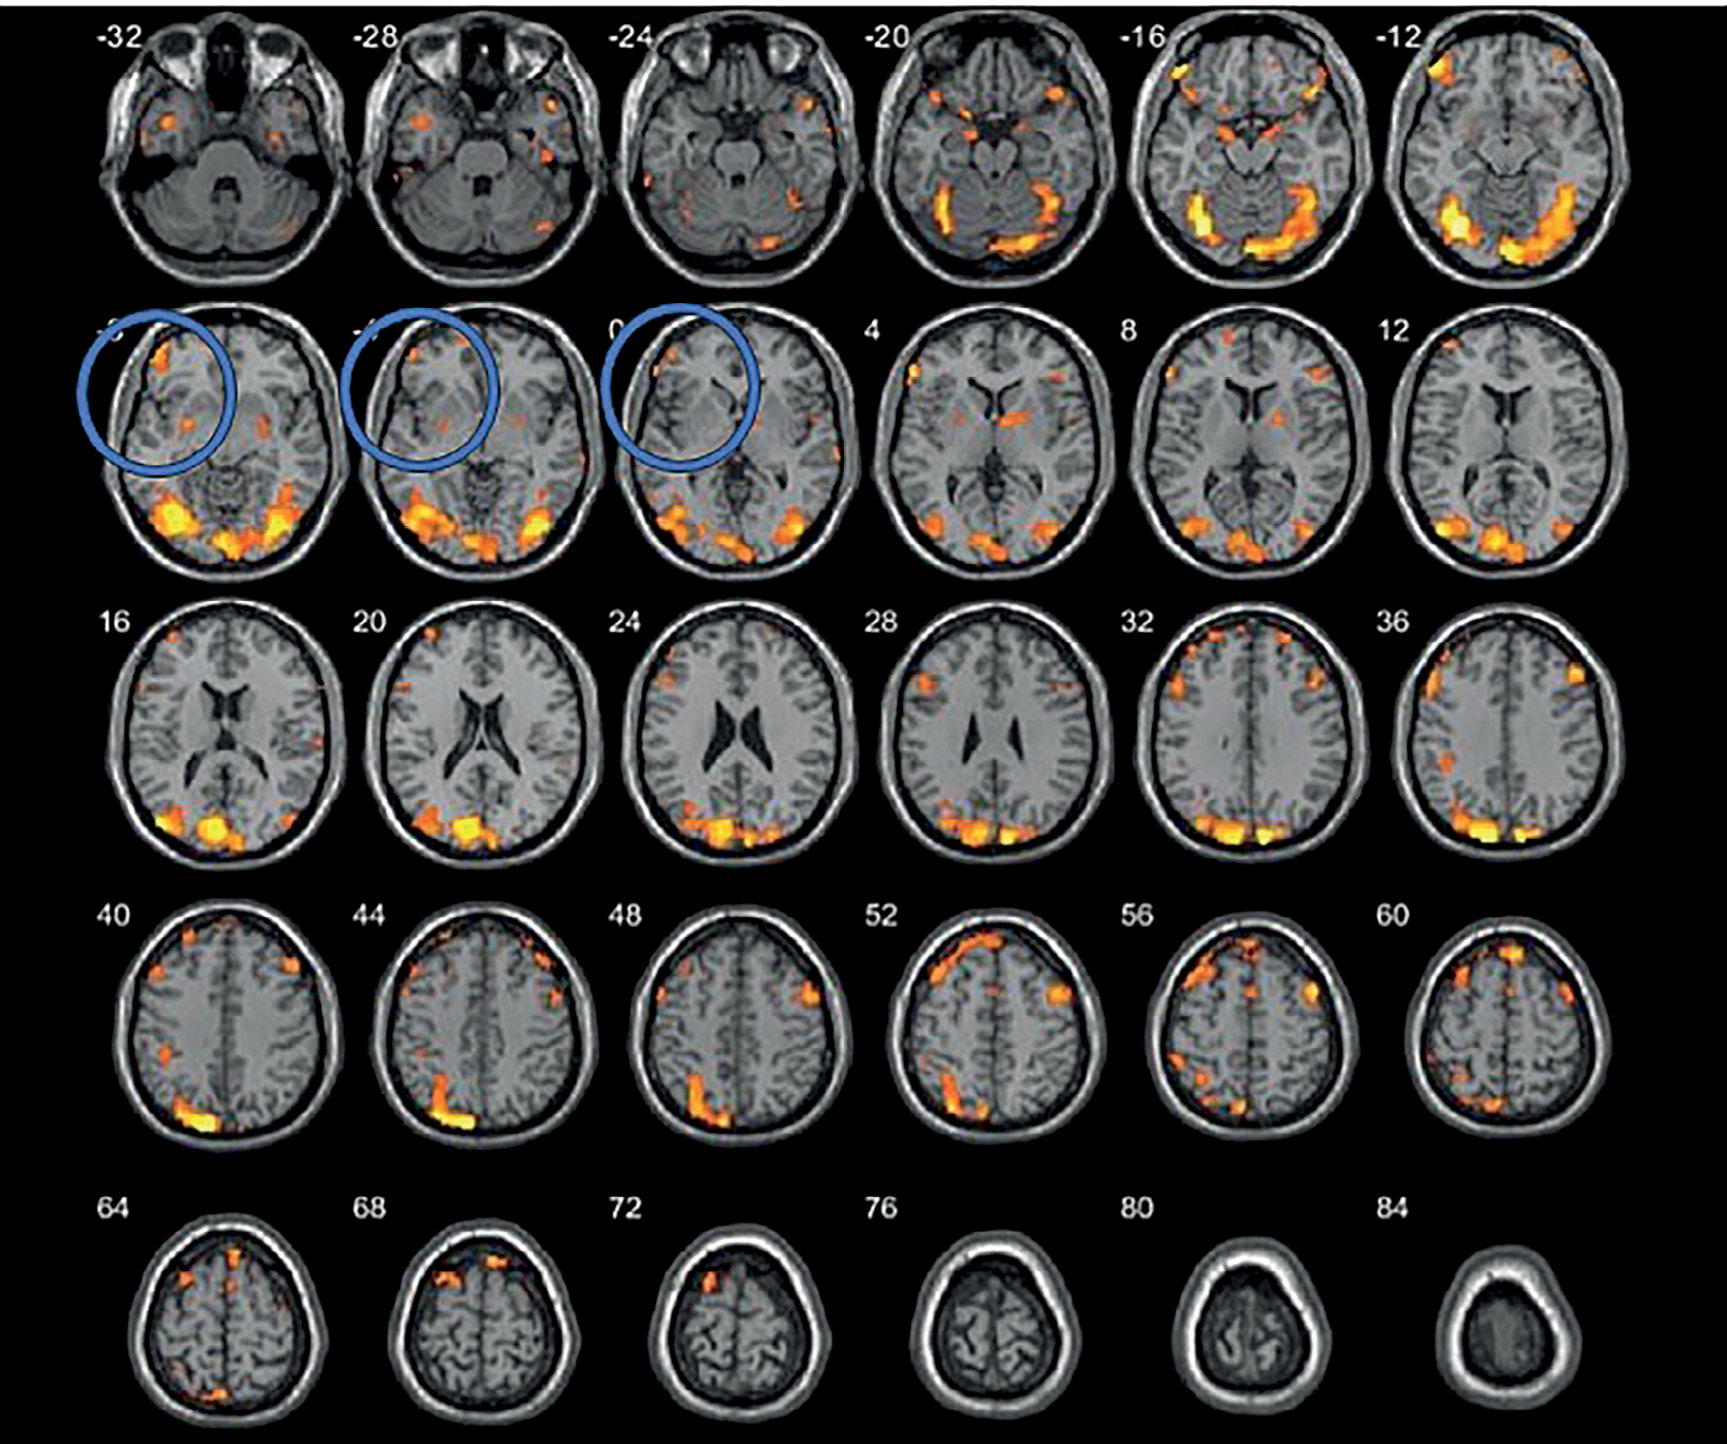

Обеим пациенткам проводилась высокочастотная ритмическая нТМС левой ДЛПФК с использованием следующего протокола: частота стимуляции – 20 Гц, интенсивность стимуляции – 100% моторного порога покоя, длительность пачки стимулов – 2 с, длительность интервала между пачками – 28 с, общее количество стимулов за сессию – 2400. Моторный порог покоя определялся в «горячей точке» как минимальная интенсивности стимуляции, при которой не менее чем 5 стимулов из 10 вызывают формирование вызванного моторного ответа (ВМО) с амплитудой более 50 мкВ при условии полного расслабления исследуемой мышцы. Ритмическая нТМС проводилась на аппарате Magstim Rapid 2 (Великобритания), калиброванном под нейронавигационную систему, с использованием восьмиобразной катушки. Курс лечения обеих пациенток включал 18 сеансов, проводимых с понедельника по субботу включительно с перерывом на 1 день (воскресенье) последовательно в течение 3 нед. Важно отметить, что, в отличие от большинства исследований, в которых мишень для стимуляции выбирается стандартно по анатомическим ориентирам, в данном случае использовался персонализированный подход к подбору мишени на основе анализа данных функциональной МРТ (рис. 1, 2). МРТ-исследование проводилось на томографе Siemens MAGNETOM Verio с индукцией магнитного поля 3 Т. Для получения структурной МРТ использовался режим Т1-градиентное эхо (основные параметры режима – время повторения 1900 мс, время эхо – 2,47 мс, толщина среза – 1 мм, 176 сагиттальных срезов, полностью покрывающих головной мозг). Структурные данные в дальнейшем импортировались в систему навигационной ТМС. Для локализации мишени для стимуляции проводилась функциональная МРТ в режиме Т2-градиентное эхо (время повторения – 3000 мс, время эхо – 30 мс , толщина среза – 3 мм, 36 аксиальных срезов) с применением блоковой зрительной парадигмы собственной разработки, с чередующимся предъявлением нейтральных стимулов (спокойные пейзажи) и высококалорийной пищи (исследование проводилось натощак) (рис. 3, 4).

Рисунок 3. Данные функциональной МРТ (до лечения), синим кругом выделена область активации в зоне интереса (левая ДЛПФК) (пациентка Ш.)

Рисунок 4. Данные функциональной МРТ (до лечения), синим выделена область активации в зоне интереса (левая ДЛПФК) (пациентка Д.)

По данным фМРТ с пищевой парадигмой, на фоне проведенных сеансов рТМС определяется снижение активации в проекции левой ДЛПФК, которое в рамках настоящего исследования может быть расценено в контексте изменения пищевого поведения. У обследованных такая фМРТ картина сопутствовала снижению аппетита и уменьшению калорийности потребляемой пищи. Исследование было выполнено на следующий день после проведенного курса лечения (рис. 5, 6).